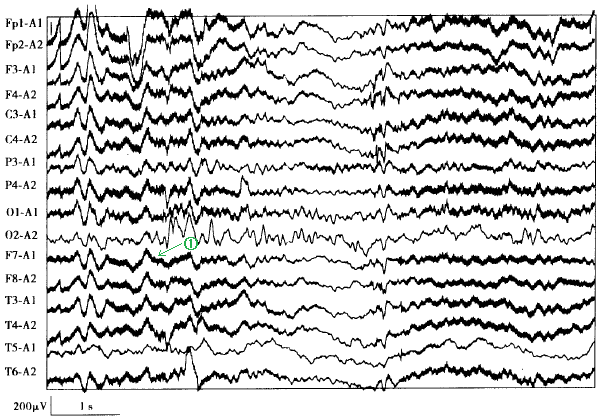

[单选题]如下图中①所示考虑为( )。A.出汗伪差B.肌电伪差C.电磁波伪差D.导线接地不良伪差E.交流电伪差